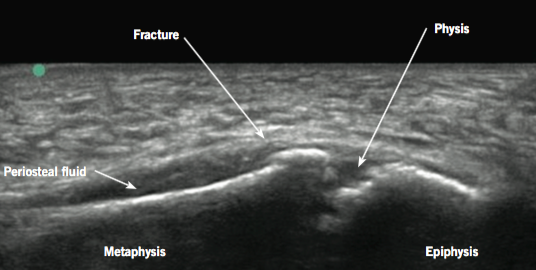

Marsha Elkhunovich, MD; Dina Seif, MD, MBA, RDMS; Mikaela Chilstrom, MD, RDMS; Tarina Kang, MD, RDMS; Thomas Mailhot, MD, RDMS

An 11-year-old boy presented to the emergency department 24 hours after a fall down several stairs.